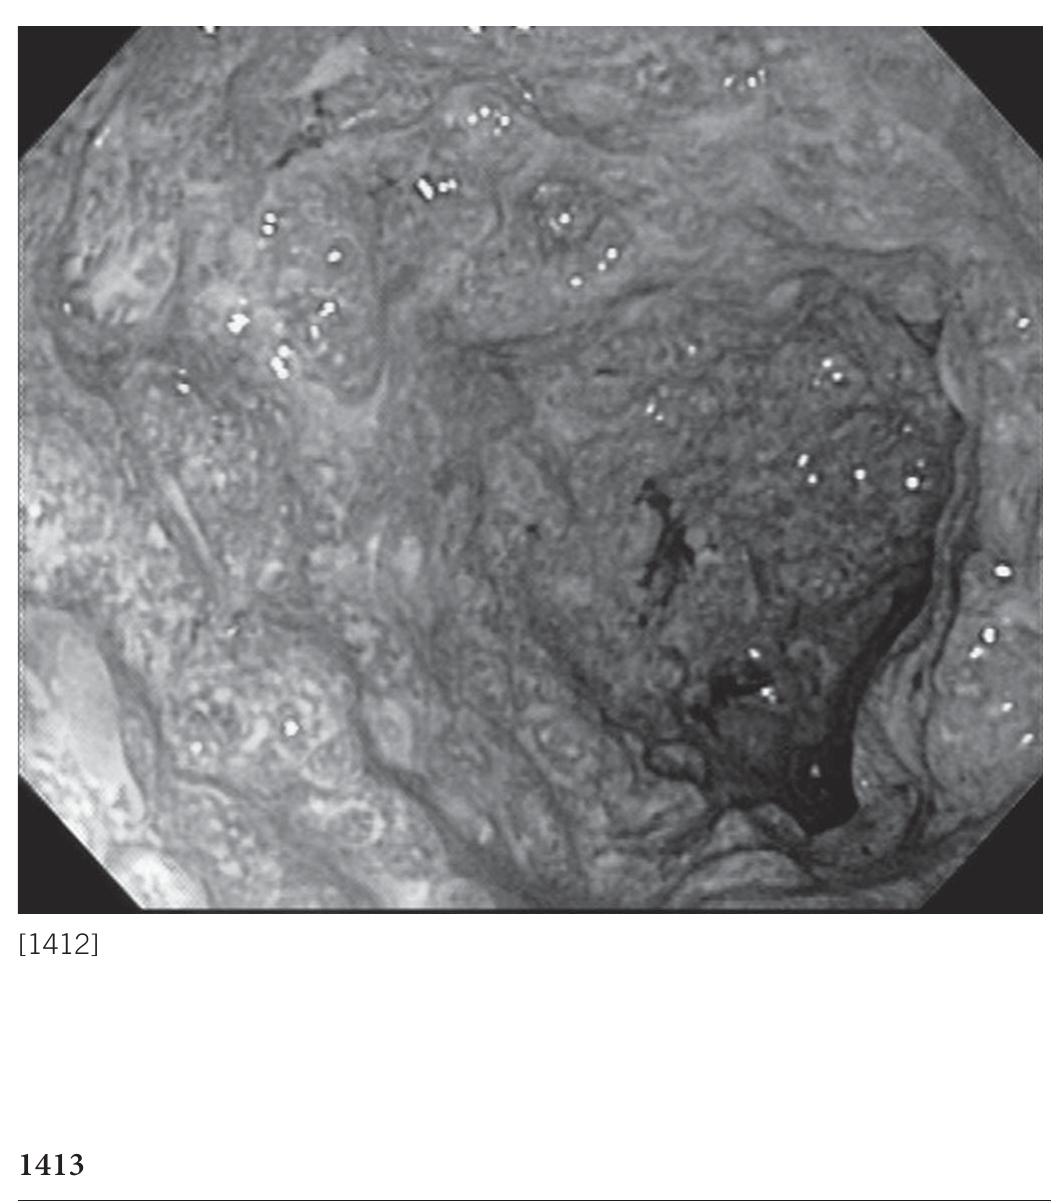

Isolated Colonic Amyloidosis: An Uncommon Cause of Chronic Diarrhea